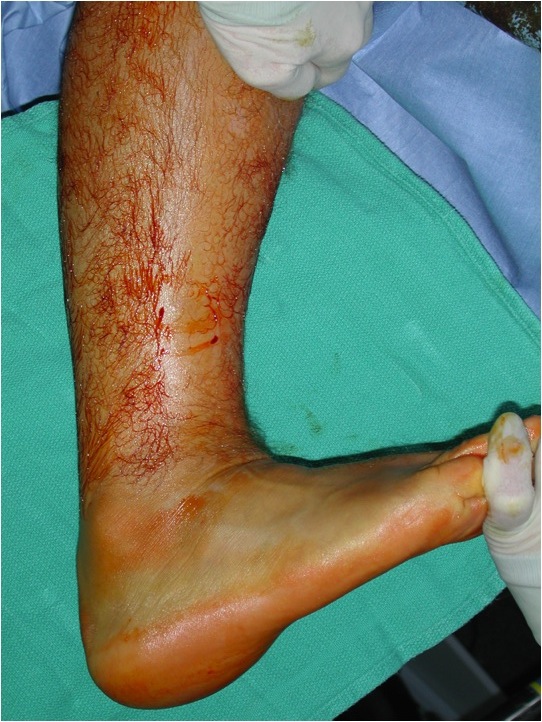

Open tendoachilles repair

Technique

Prone position with tourniquet

- slightly medial incision to protect sural nerve

- full thickness skin flaps to paratenon

- identify and protect sural nerve

- divide paratenon longitudinally

- can incise paratenon in the midline anteriorly which increases tissue available for closure

- Bunnell Suture / Krackow suture x 2 with high strength suture / fibre wire

- one in proximal and one in distal tendon ends

- tie via two knots with foot fully plantar flexed

- +/- augment with circumferential 4.0 suture to minimize bunching

- careful closure of paratenon to prevent skin adhesions

- front slab in plantarflexion 2 weeks

- then standard accelerated rehabilitation

Anterior release of paratenon to allow posterior closure over achilles repair

Repair with proximal and distal Krackow high strength sutures